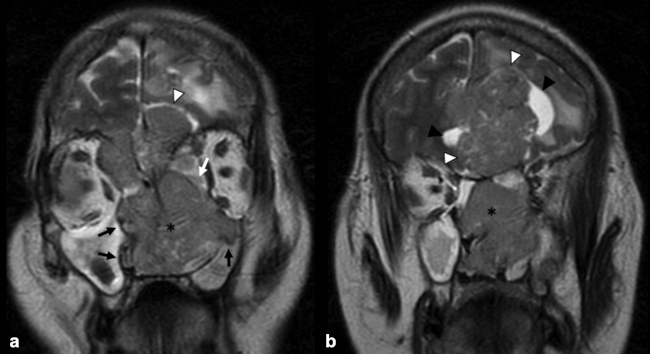

La RM es la prueba de imagen de elección para evaluar los detalles de la extensión y la estadificación locorregional del tumor. La RM es superior a la TC para determinar el grado de afectación del tejido blando (►Fig. 9) con una mejor evaluación de la afectación intracraneal (►Figs.10,11,12,13,14), orbital (►Figs.14y15), de la base del cráneo y la invasión perineural.53,54 La RM tiene un valor añadido para distinguir la afectación dural de la del parénquima cerebral (►Fig. 12).55 En la RM, el NBO aparece hipointenso respecto a la sustancia gris en imágenes ponderadas en T1 y de isointenso a hiperintenso en las imágenes ponderadas en T2 (►Figs.10,11,12,13,14,15).56 Muestra un realce homogéneo, excepto en áreas con hemorragia o necrosis. Además, permite diferenciar las secreciones retenidas del tumor, al ser estas hiperintensas ponderadas en T2.53,55 Los hallazgos de imágenes clásicos incluyen una masa “en forma de mancuerna” que se extiende a través de la placa cribiforme (►Fig. 12), con la parte estrecha a nivel de la placa. Los quistes tumorales periféricos (►Figs.5b,12,14,16) y las calcificaciones moteadas son bastante característicos de NBO.1

Las secuencias de RM con saturación de la grasa ayudan a diferenciar el tumor de la grasa orbital y los músculos. Un margen suave de la interfaz tumor-grasa sugiere que la lesión está contenida en la fascia periorbital (►Fig. 15), mientras que un margen irregular favorece la invasión franca de la órbita.35,49,57 Sin embargo, el diagnóstico definitivo de invasión de la duramadre y los tejidos periorbitarios solo es posible en la cirugía.49